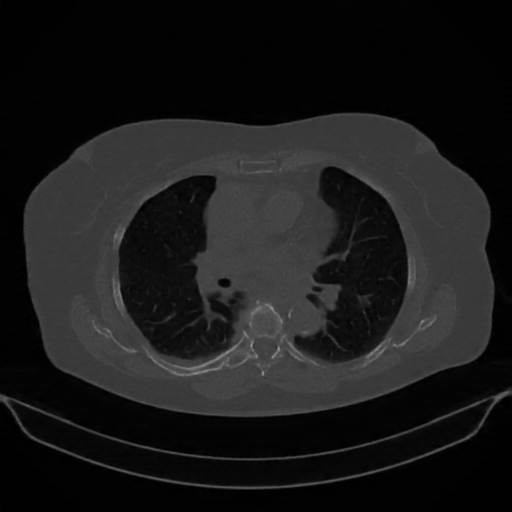

Original NATIVE CT scan (input)

Lung window (WL -600, WW 1500 β†’ Low βˆ’1350, High +150)

Mediastinum window (WL 40, WW 400 β†’ Low βˆ’160, High +240)